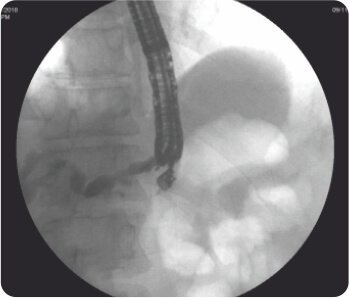

পেট থেকে IHBRD এর EUS নির্দেশিত খোঁচা

চোলাঞ্জিওগ্রাম